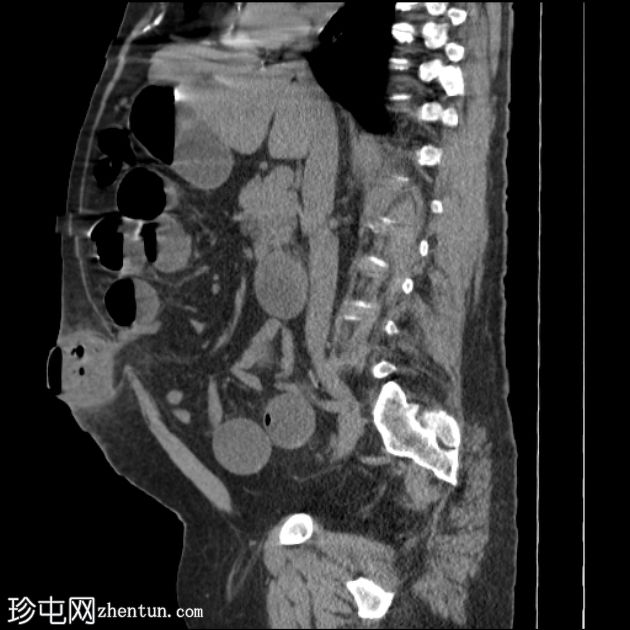

矢状位

平扫

定位片显示多处扩张的小肠袢。侧位片显示脐部皮下透光区(脐疝)。

多处扩张的小肠袢内可见多个气液平面,直至进入脐疝的肠袢处可见移行点,而从疝口出来的远端小肠袢则呈塌陷状态。

诊断:嵌顿性脐疝继发急性小肠梗阻。